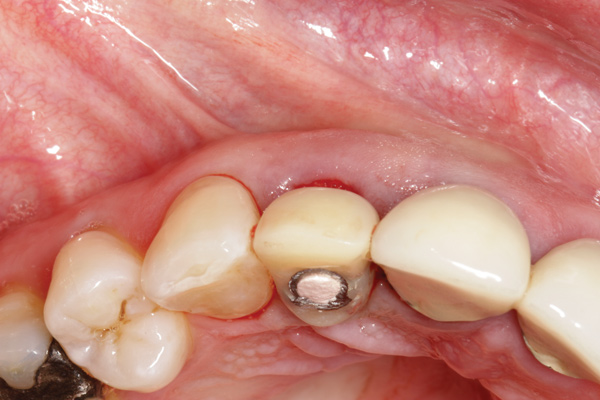

Fig 5. Atraumatic extraction without raising the flap, with the intention of minimizing bone loss, especially in the interproximal area.

Figure 5

Fig 6. Implant was placed in an ideal 3-dimensional position.

Figure 6